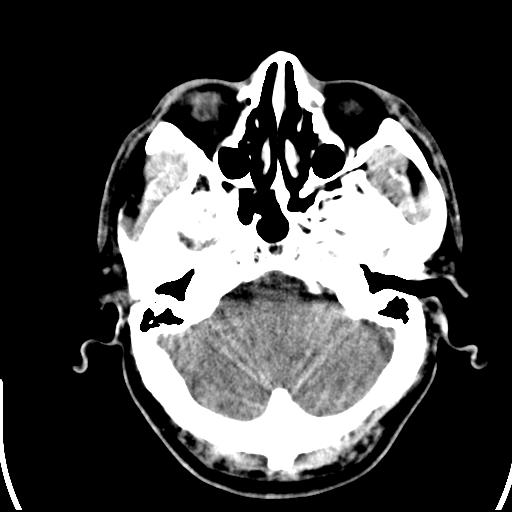

标题: CT25435:头皮下高密度影???

头皮下高密度结节影???临床上在老年男性比较常见。大家看看是什么?成因是? 本例患者,男性,51岁。外伤来诊。无染发史及发根植入史。